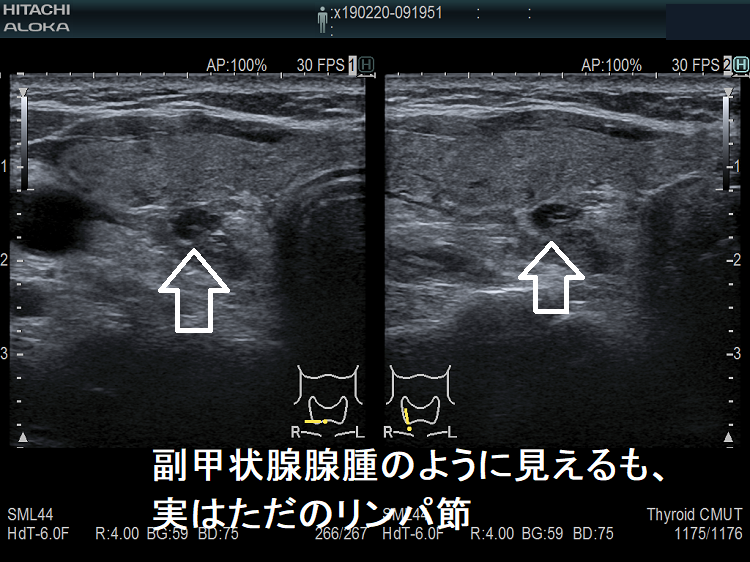

副甲状腺腺腫のように見えるも、実はただのリンパ節

副甲状腺腺腫との違いとして、リンパ節では

- 内部血流が無く

- リンパ門が存在します(ここだけ血流があります)

ケース①②